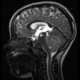

Teratoid tumor

An atypical teratoid rhabdoid tumor (AT/RT) is a rare tumor usually diagnosed in childhood. Although usually a brain tumor, AT/RT can occur anywhere in the central nervous system (CNS), including the spinal cord. [Source: Wikipedia ]